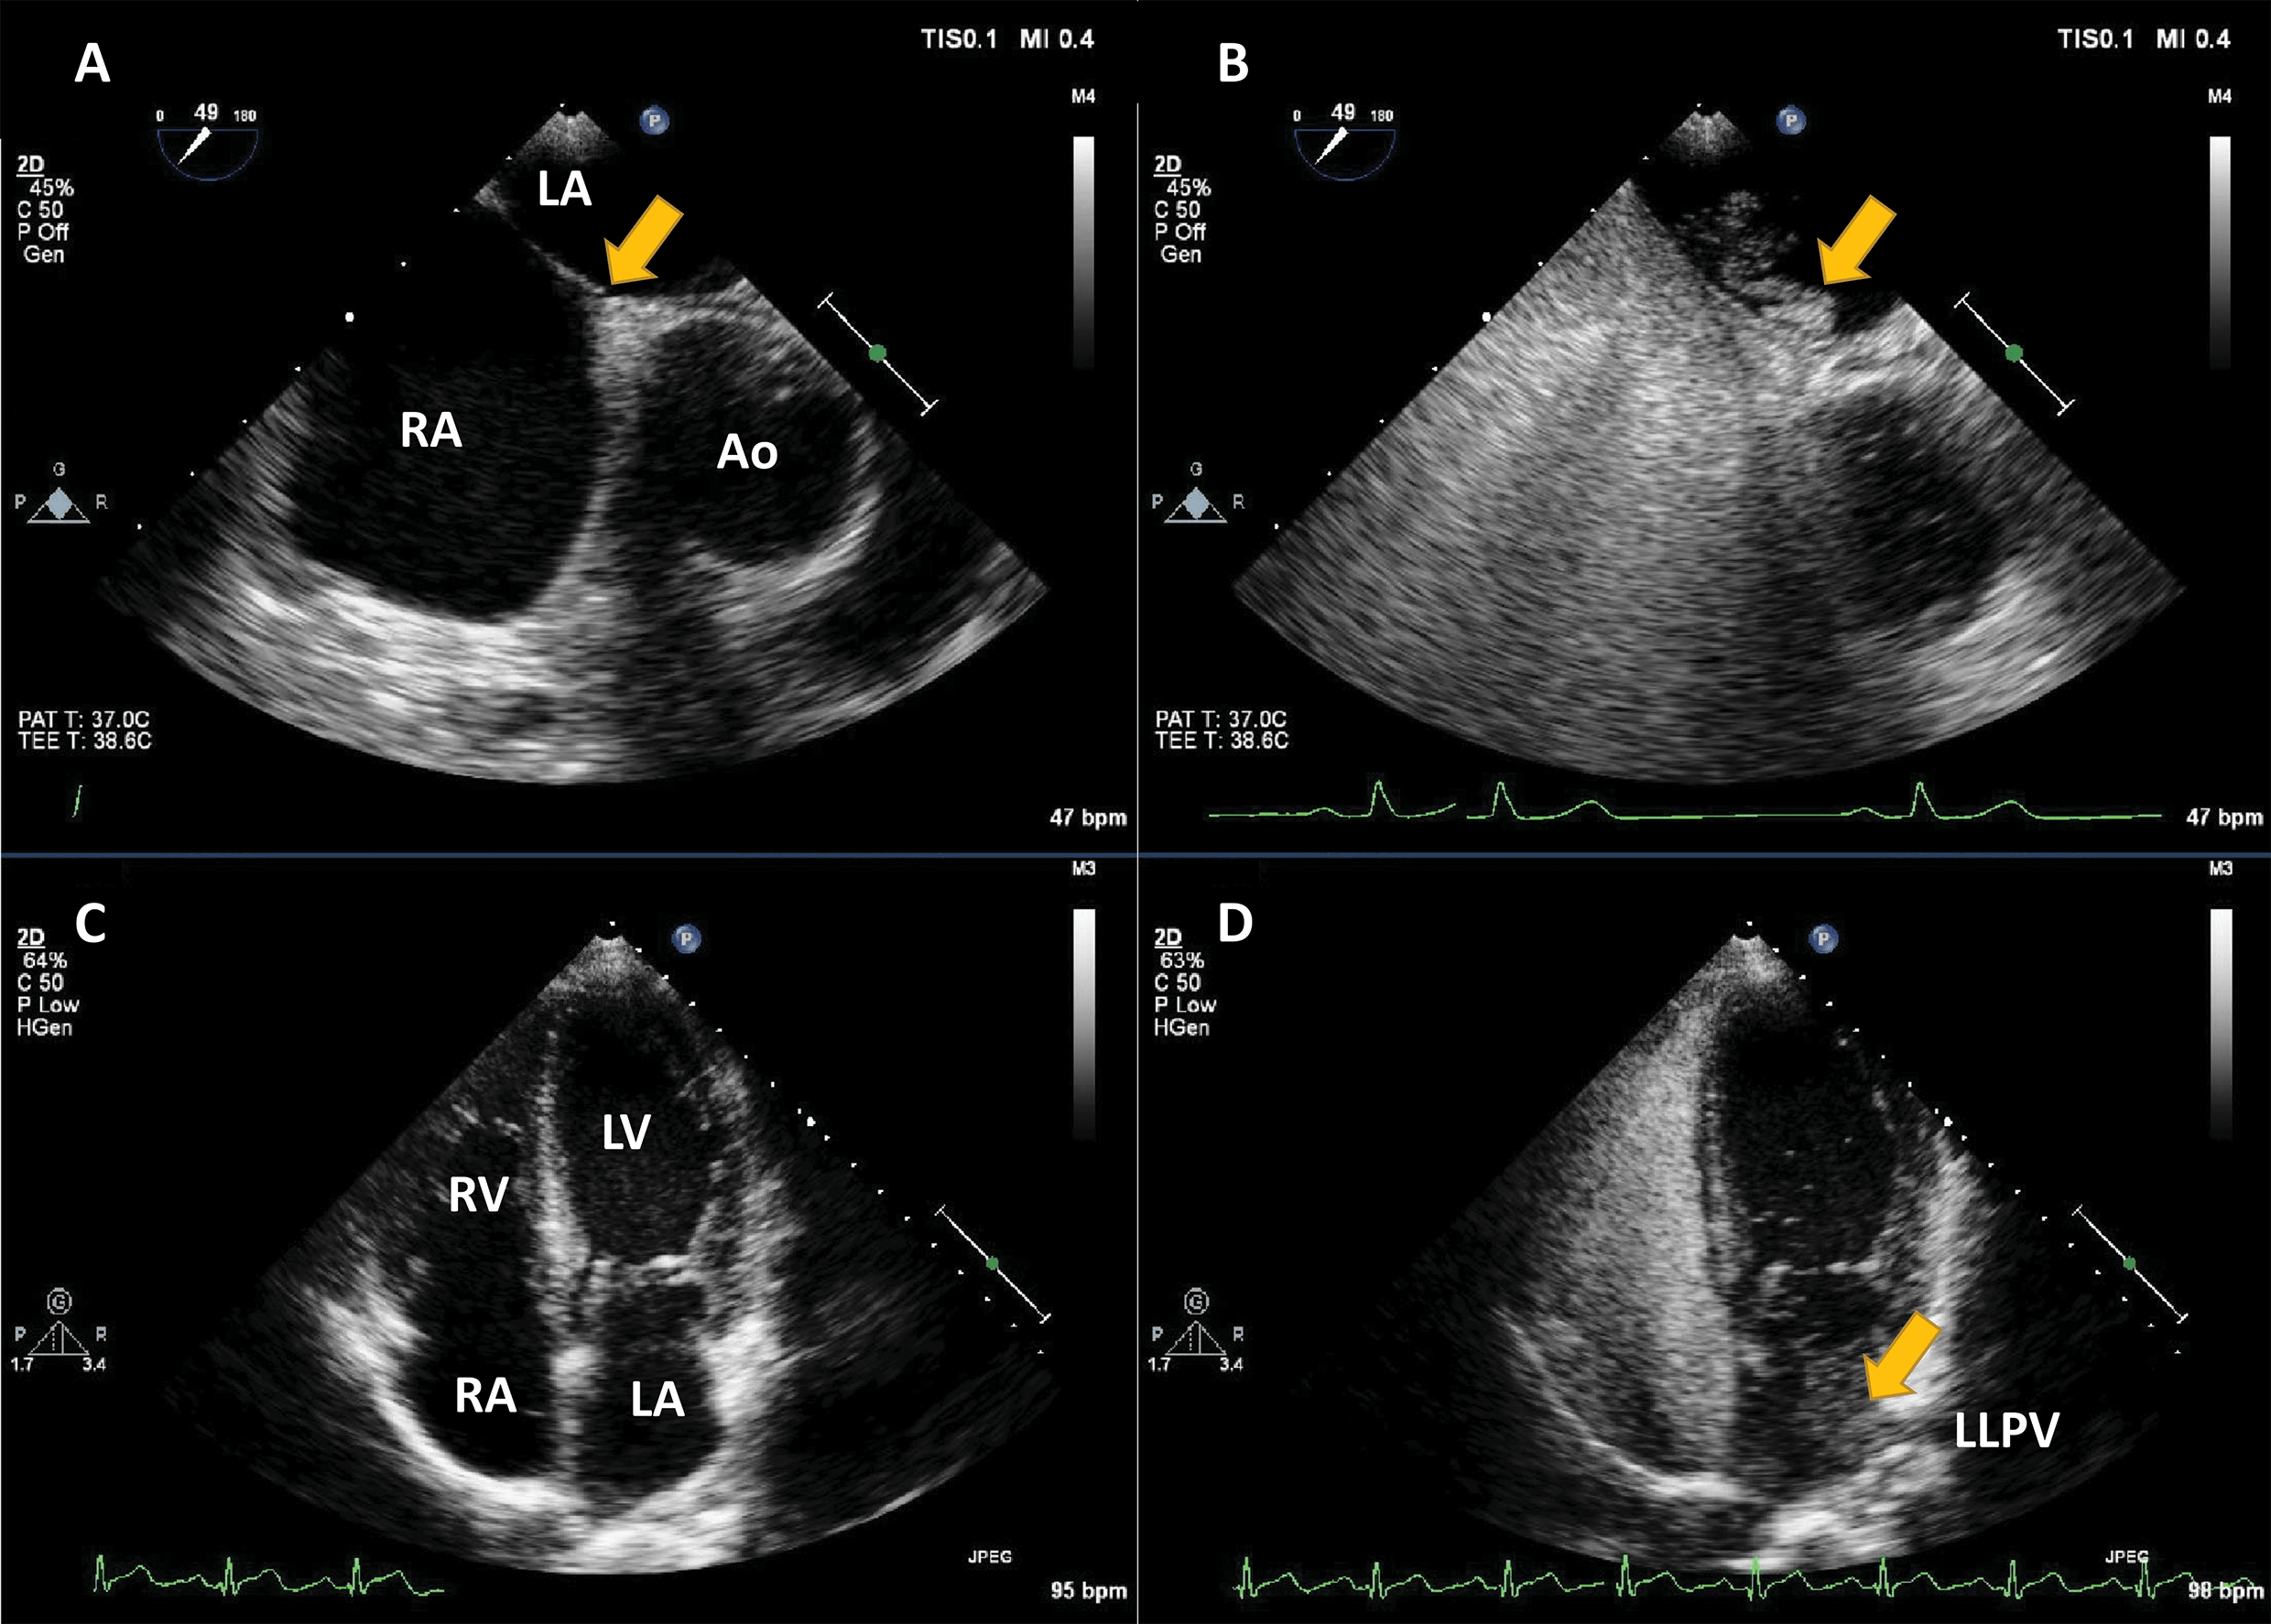

The largest body of evidence for MEE concerns the indication for LVO for enhancing the endocardial borders [10, 11, 12, 13, 14, 15]. This is achieved by using repetitive intravenous boluses of UEA, and sometimes continuous low-dose infusion. Guidelines indicate the use of LVO to enhance the endocardial borders in cases when the LV dimensions, function or regional wall motion cannot be accurately assessed using non-enhanced ultrasound [7, 14]. The general “rule of thumb” is to use microbubble UEA in cases where two or more contiguous myocardial segments are not properly visualized with non-enhanced ultrasound [13]. Of course, recent years have seen tremendous improvement in image quality for clinical ultrasound systems. But despite the introduction of harmonic imaging as a standard, some images remain non-diagnostic (Fig. 2). Moreover, harmonic imaging represented a significant leap in MEE [16, 17], leading to the present-day contrast-specific imaging modalities.

Fig. 2.Left ventricular opacification (LVO) for endocardial border delineation. Example of baseline non-enhanced echocardiography images in apical 4-chambers (A) and apical 2-chambers (B) views, where the visualization of the endocardium is suboptimal over several segments. After intravenous injection of a bolus of UEA, there is full opacification of the LV cavity, with clear delineation of the endocardium in all segments (C, D). Source: personal collection.